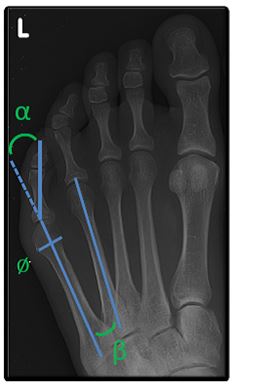

Een bunionette is een pijnlijk uitstekende knobbel net voor de kleine teen.

Die bunionette ontstaat meestal door een lichte scheefstand van het vijfde middenvoetsbeentje en overdruk van te smal schoeisel.

De belangrijkste behandeling bestaat uit goed schoeisel eventueel aangevuld met steunzolen. Bij ernstige pijnklachten of last kan een ingreep wenselijk zijn. Via een incisie van 2 à 3 mm brengen we een klein boortje in. We zagen hiermee een middenvoetsbeentje door, om de voet wat smaller te maken.